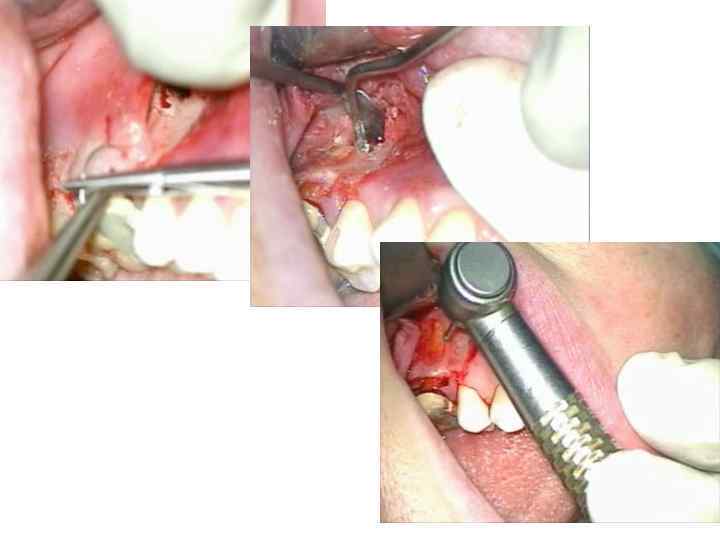

• После консервативного лечения и пломбирования остающихся каналов корней и полости коронки зуба отделяют и осторожно удаляют при помощи бора на уровне бифуркации корней часть коронки и корень с патологическим очагом. При удалении части коронки и корня зуба используют чаще щипцы, производя ими ротационные или легкие люксационные движения. При удалении корня элеватором надо правильно определить точку опоры и с большой осторожностью работать на кости, не травмируя межкорневую перегородку и костный сегмент в области оставшегося корня. При работе с помощью боров, дисков при гемисекции обязательно охлаждение операционного поля путем орошения изотоническим раствором хлорида натрия из шприца или через специальную систему

Ампутацию корня зуба производят, предварительно отделив его у места фуркации. Показания и противопоказания к ампутации корня те же, что и при гемисекции. Удаляют чаще всего один из щечных корней верхних больших коренных зубов. Выполняют трапециевидный или углообразный разрез и отделяют слизисто-надкостничный лоскут вестибулярной или небной поверхности альвеолярного отростка верхней челюсти. Лоскут должен быть несколько больше зубочелюстного сегмента, где расположен корень, чтобы потом перекрыть образовавшийся дефект кости. Корень отсекают фиссурным бором, удаляют при помощи щипцов, делая только ротационные движения. В отдельных случаях удаляют переднюю костную стенку альвеолы и отсеченного корня с помощью элеватора.

Методика операции • Операцию проводят под проводниковой и инфильтрационной анестезией. В области наружной поверхности альвеолярного отростка делают дугообразный, линейный, углообразный или трапециевидный разрез с таким расчетом, чтобы при зашивании раны линия разреза не проходила на уровне трепанационного отверстия, а лоскут перекрывал его своими краями

Отделив от кости с помощью распатора слизи-стонадкостничный лоскут, его оттягивают по направлению к переходной складке тупым или острым крючком, трепанацию наружной стенки зубной альвеолы производят крупными шаровидными, а также фиссурными борами. Обнажив таким путем окруженную грануляционной тканью верхушку корня, приступают к его удалению. Корневую верхушку следует спиливать фиссурным бором или торцовой фрезой, после удаления верхушки зуба выскабливают из полости грануляции и участки размягченной кости кюретажной ложкой

сошлифовав фрезой несколько наискось культю корня, небольшим шаровидным бором расширяют просвет канала, затем обратно-конусовидным бором или ультразвуковой насадкой формируют в культе полость, выполняют ее серебряной амальгамой, стеклоиномерным цементом, МТА цементом, вводя небольшими порциями и конденсируя инструментом